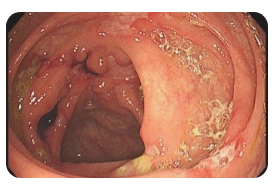

💩 왼쪽 옆구리 통증 설사

설사와 함께 왼쪽 옆구리 통증이 발생한다면 대장과 관련된 질환을 고려해볼 수 있습니다. 과민성 대장 증후군, 게실염, 크론병 등이 주요 원인입니다. 이들 질환은 장내 염증이나 긴장으로 인해 왼쪽 하복부 및 옆구리에 통증을 유발합니다. 스트레스나 식습관에 따라 증상이 심해지며, 설사와 변비가 번갈아 나타나기도 합니다. 장기간 증상이 지속되면 대장 내시경 검사를 통해 정확한 진단이 필요합니다.